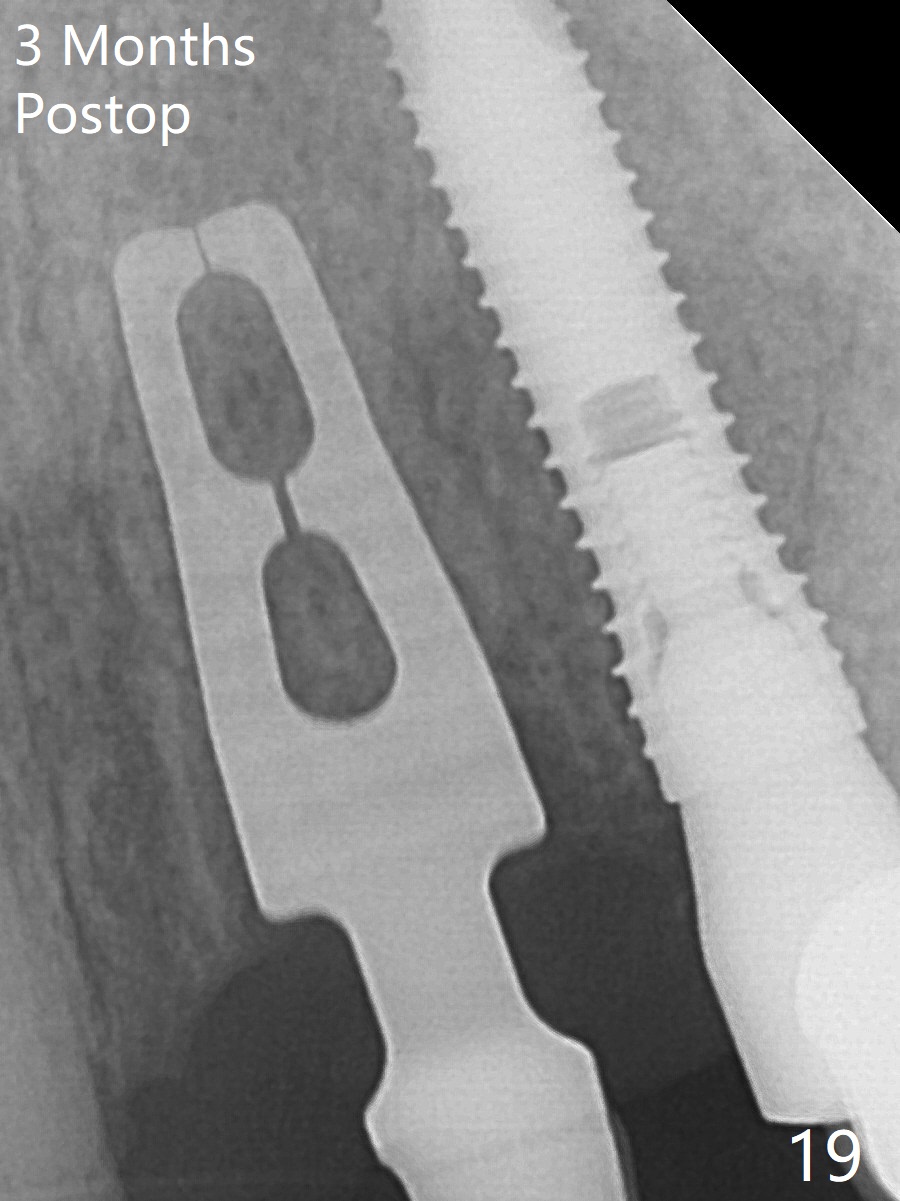

The mesiobuccal margin at #8 is redefined 4 weeks postop (Fig.14) so that the cervical end of the temporary crown is able to move mesially (Fig.13). The most coronal portion of the bone graft at #11 begins to be detached (*). The mesial portion of the abutment at #10 will be removed (curved white line) in the following week. After removing the most coronal portion of detaching bone graft at #11, acrylic is added to form a concave pontic (Fig.15 ^). With removal of the mesial portion of the abutment at #10, the retainer is moved distal (>). Pontics form at UL1 and 3 two months postop (Fig.16 *), while there is buccal atrophy at UL1,2 (Fig.17). 术后3个月植牙区牙龈形态良好(图十八),即将暴露,放置愈合基台。图十九是在右上1根管治疗时(基台放置后五天)拍摄。左上3术后3个月3个星期,1,2唇侧塌陷(图二十)。叶状植体处牙槽嵴往根尖萎缩(图二十一:^)。尽管做了松弛切口,放入事先预备的粘性骨粉后,几乎没有空间放置结缔组织移植物,恰好还没有取。放置PRF膜后,使用4-0 Monoglyc缝线缝合。牙龈似乎冠方移位(图二十二:箭头)。植骨后,唇侧仿佛饱满多了(图二十三:*)。骨粉放置于左上1,2唇侧和牙槽嵴(图二十四:*,与之前(图十九)对比)。后者有助于牙龈冠方移位,而前者有助于增加唇侧饱满度。植骨术后两周唇侧仍饱满(图二十五,六)。植骨后四个月牙冠粘固,两个月后,病人抱怨10号牙左右食物坎塞(图二十七),9/10牙冠撤除,10基台边缘加深,重做临时牙冠,同时增加9凹陷(pontic)。一个月后,9/10临时牙冠修整两次,11永久性牙冠撤除,也制备临时牙冠,外形明显改善(图二十八)。